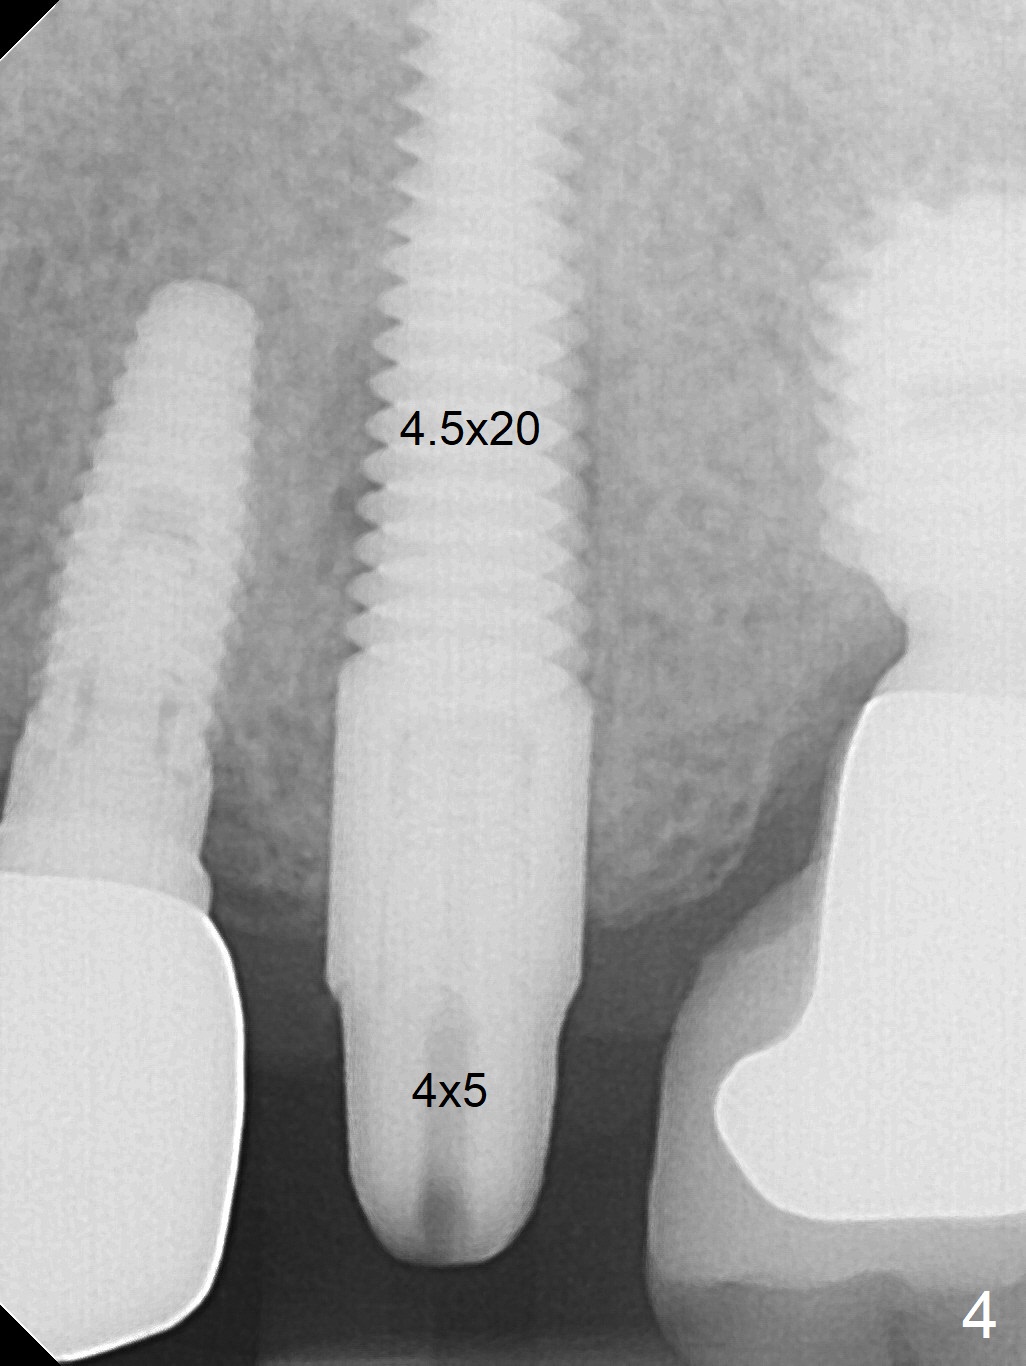

When the tooth #13 with buccal fistula is extracted, the root is found to have vertical fracture (Fig.1). The socket is 14 mm deep (gingival level); the initial osteotomy depth is 20 mm (6 mm to be in the native bone for primary stability, Fig.2). A 4.5x20 mm tissue-level implant (>60 Ncm) is going to be placed in the palatal aspect of the oval socket (Fig.3-5). The localized defect in the buccal plate as indicated by labels (* (Vanilla/Osteogen), B (buccal) and < (perforation) in Fig.6,7 (CBCT coronal and axial sections) is repaired by the bone graft. The bone and gingiva are healthy around the implant nearly 4 months postop (Fig.8,9).